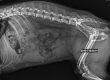

如图所示,L=5.8v,S=4.6v,VHS=L+S=10.4v。

3、X线片的实际测量

如上图,VHS=5.7v+4.5v=10.2v

如上图,VHS=5.2v+5.0v=10.2v

这是一只京巴犬,因为剧烈咳嗽而就诊,经检查确诊为心衰。

如上图,VHS=5.6v+5.9v=11.5v